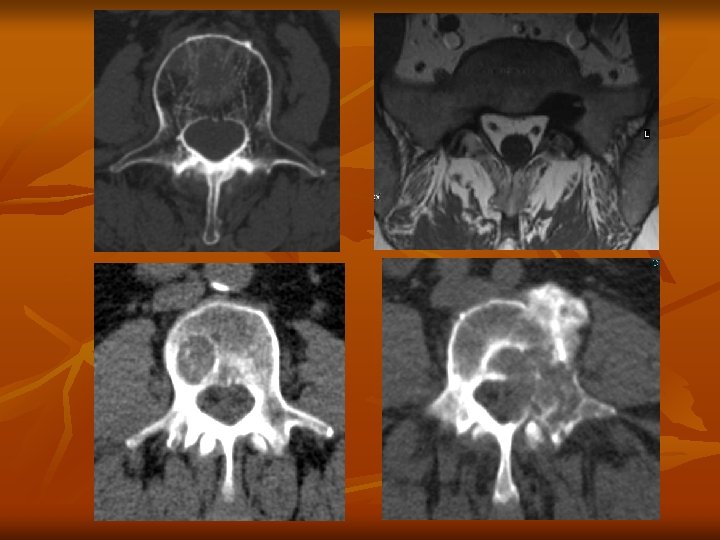

Daganatok n n n n n Ritka, de súlyos kórkép Jó és rosszindulatú daganat Fájdalom, mely nem specifikus Csontszerkezet destrukciója, instabilitás Myelon és ideggyök kompresszió Patológiás törés Rtg CT és MR Scintigráfia

Tumorok • • • Extraduralis – csonttumorok – metastasis – neurinoma Intraduralis - extramedullaris – meningeoma – neurinoma Intramedullaris – astrocytoma – ependymoma – haemangioblastoma